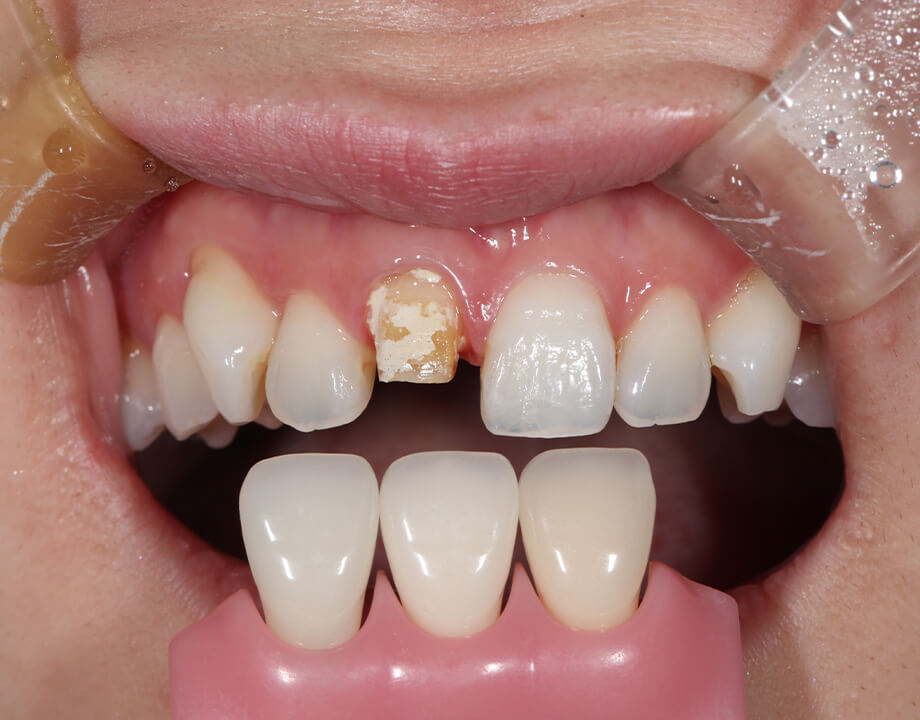

Case 01天然歯

ジルコニアレイアリング